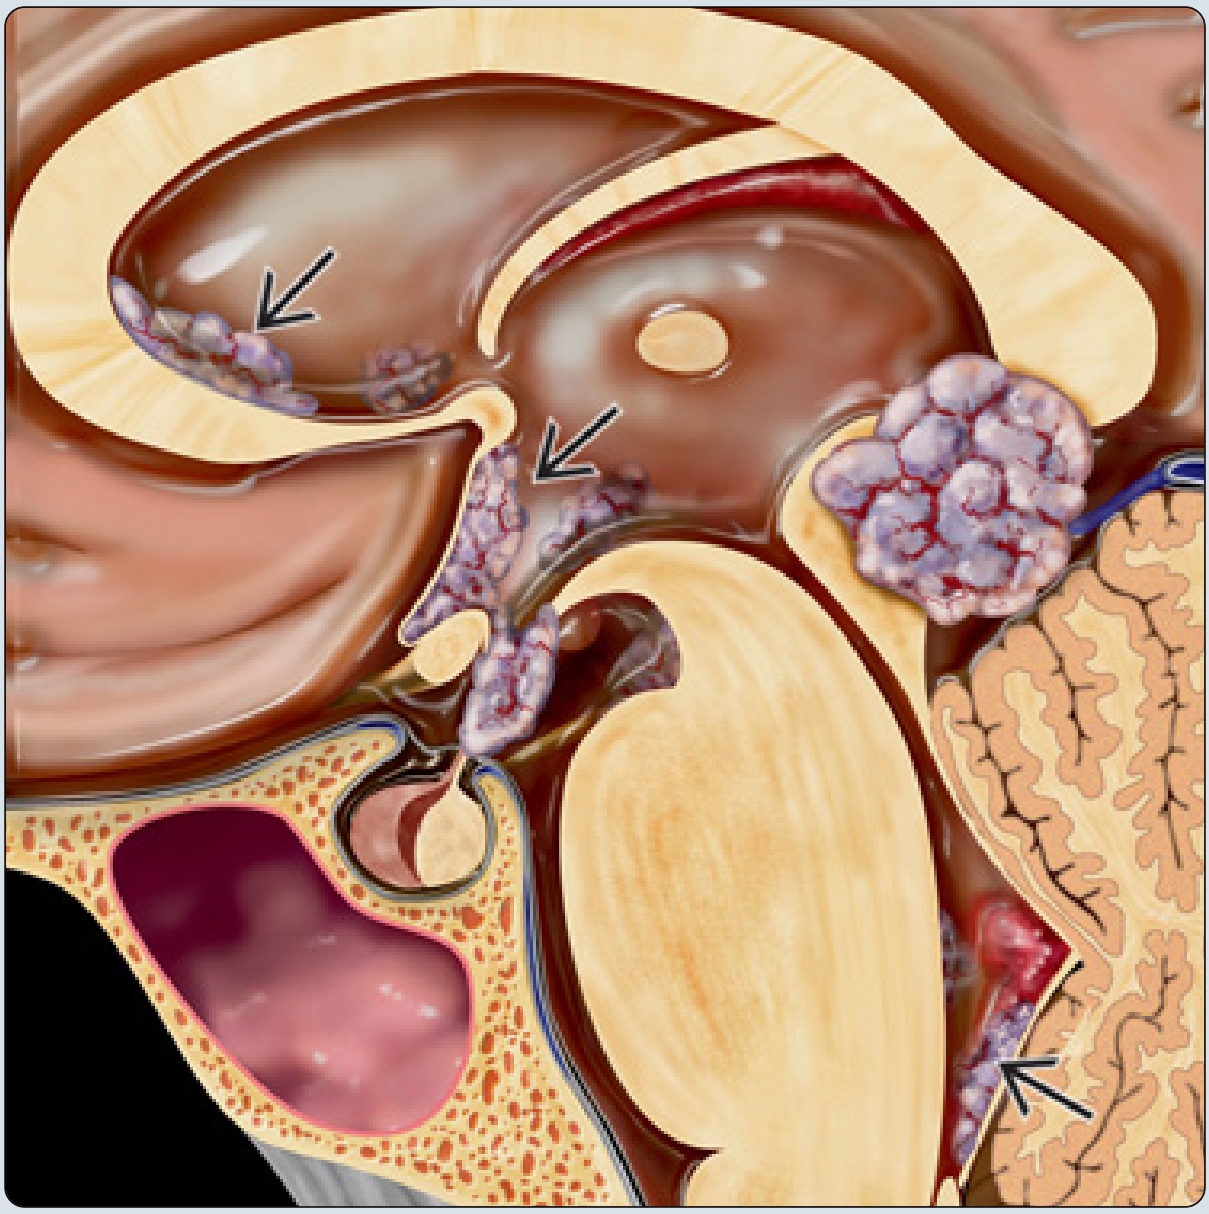

轴位CT扫描示典型的松果体生殖细胞瘤,可见边界清楚的稍高密度肿块包绕钙化的松果体。

生殖细胞瘤还有两个好发部位,一个是松果体区,其常常包绕松果体本身钙化,而另一个好发部位是基底节区,其几乎只见于男性,其常伴患侧邻近脑实质、脑干萎缩,可见华勒氏变性。